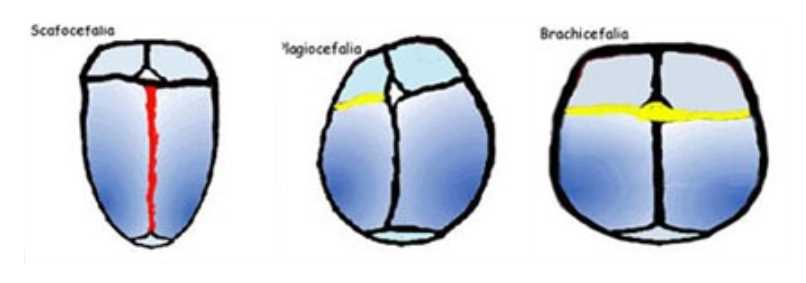

Il neonato subisce delle compressioni importanti dal momento in cui si incanala fino alla nascita soprattutto a livello del cranio, che sovente assume delle forme particolari che testimoniano il maltrattamento subito.

Queste “ deformazioni” momentanee sono dovute alla grande plasticità delle ossa della scatola cranica che risulta essere fondamentale per permettere il passaggio dalla vita intrauterina al mondo esterno.

Il più delle volte, grazie all’avvio del meccanismo respiratorio, al pianto ed alla suzione, la testolina ritrova la sua forma nel giro di qualche giorno.

Capita però che da solo il corpo non riesca a reagire a questo stato di “compressione” ed abbia bisogno del lavoro osteopatico per facilitare il recupero.

Di seguito alcuni esempi delle forme che può assumere la testolina del neonato nei primi mesi di vita ( visione dall’alto):